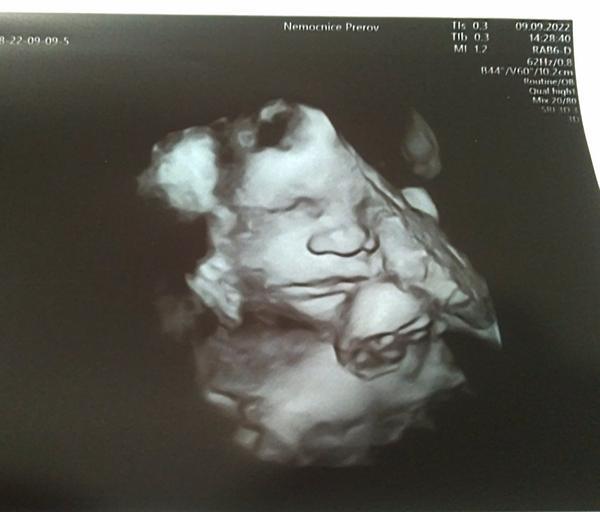

Odpovídá 4D ultrazvuk reálnému obrazu plodu?

Zdravím, včera jsem byla na 4D ultrazvuku. Jsem v 28.týdnu, vzhledem k tomu, že mám placentu na přední straně, tak ten obraz nebyl nejlepší.

Prý má 1kg. Přijde Vám, že je na svoje ,,stáří” dost malinký? Na 4D ultrazvuku jsme byla poprvé a nevím ,jak moc tedy obraz odpovídá realitě. Podle obrázku to vypadá, že prakticky nemá žadné rtíčky.😅

Malinký mi nepřijde, nejvíc se nabírá v posledním trimestru, kdyby bylo něco špatně, tak by to Dr určitě řešil. Jinak odpovídání vzhledu i celkem sedí, je to takové kostrbaté, ale třeba nos a rty na těch 3D fotkách moje děti měly už jako při narození :D